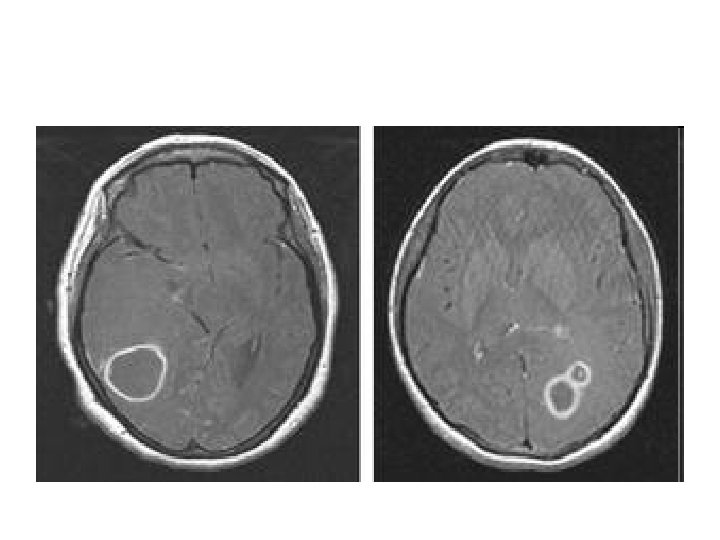

DIAGNOSIS • The diagnosis is established by a computed tomography (CT) (with contrast) examination. • At the initial phase of the inflammation (which is referred to as cerebritis), the immature lesion does not have a capsule and it may be difficult to distinguish it from other space-occupying lesions or infarcts of the brain. • Within 4– 5 days the inflammation & dead brain tissue are surrounded with a capsule, which gives the lesion the famous ring-enhancing lesion appearance on CT examination with contrast (since intravenously applied contrast material can not pass through the capsule, it is collected around the lesion and looks as a ring surrounding the relatively dark lesion).

DIAGNOSIS • Ring enhancement may also be observed in cerebral hemorrhages and some brain tumors. • However, in the presence of the – – rapidly progressive course with fever, focal neurologic findings (hemiparesis, aphasia) & signs of increased intracranial pressure, the most likely diagnosis should be the brain abscess.